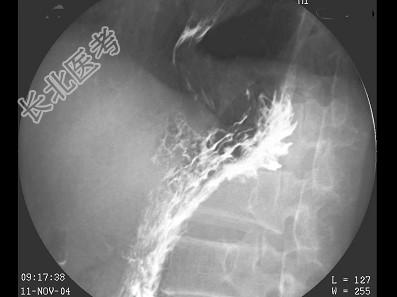

- 单项选择题男,59岁, 进行性吞咽困难半年,结合图像, 最可能的诊断为 ( )

D、食管癌

E、贲门癌侵及胃底、食管下段